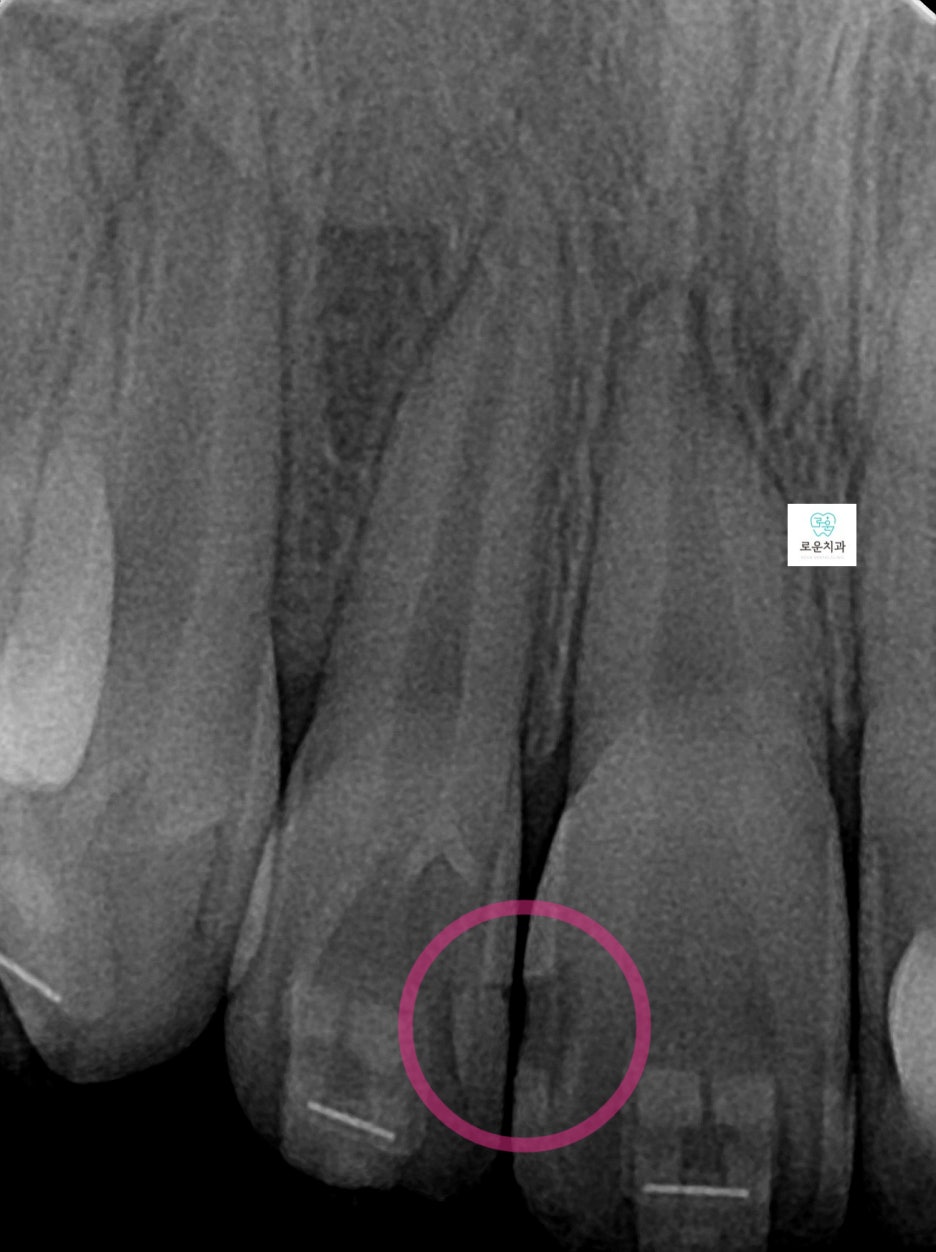

엑스레이 촬영 결과

인접면 충치가 더욱 명확하게 확인되었으며

깊이에 따라 마취 후 치료를 진행했습니다.

앞니에 생긴 우식은 치아 4개에 사이에 생겨 총 6면의 우식이 발생

→ 치아는 붙어 있는 면 양쪽으로 우식 진행되기 때문에 면수로 진행